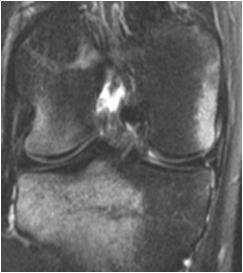

При остром повреждении ПКС представлена в виде разволокненных тонких волокон или извилистой линии или чрезмерно вогнутой верхней тени связки. Часто обнаруживается гематома в области бедренного прикрепления связки, локализации наиболее частого места разрыва (рис. 35).

Рис. 35. МРТ коленных суставов: стрелкой указаны разрывы передней крестообразной связки и гематома.